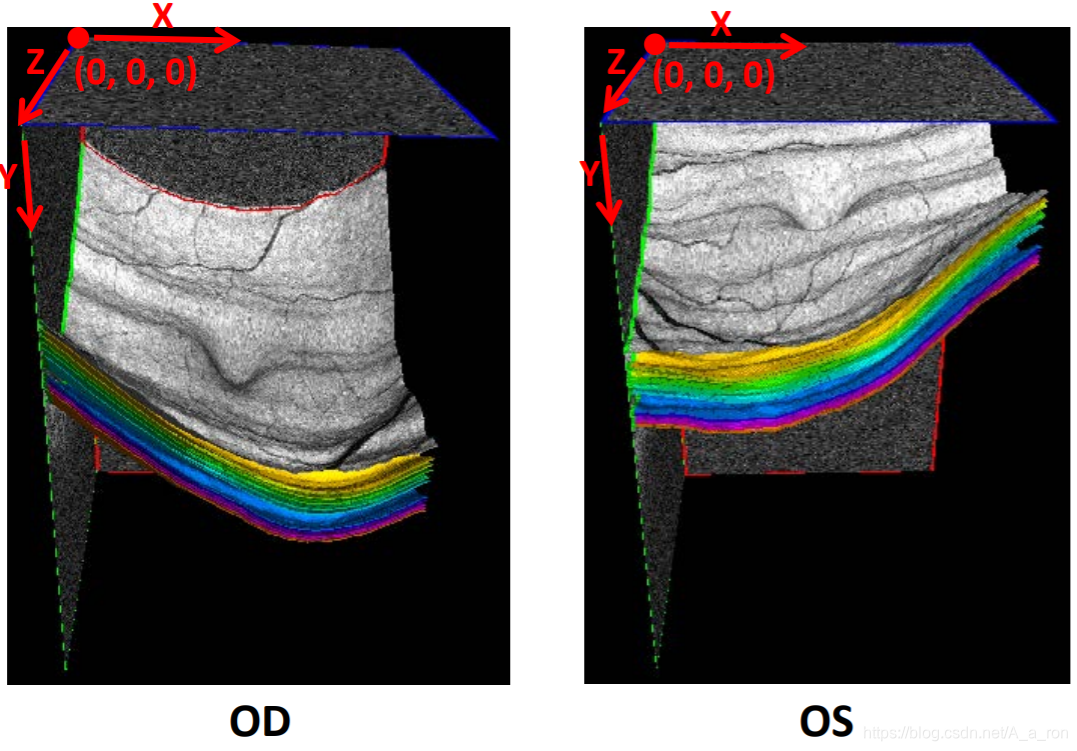

2. OCTExplorer

三维可视化: